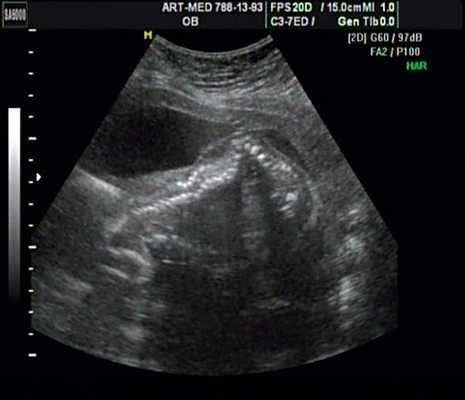

Беременная М., 21 года. Впервые обратилась в клинику в срок 20 нед беременности. Исследование проводилось на аппарате SonoAce-R7 (Samsung Medison) с использованием режима поверхностной объемной реконструкции 3D/4D. При изучении позвоночника плода в трех плоскостях костных деформаций не выявлено. В грудном отделе позвоночника обнаружено тонкостенное кистозное образование с анэхогенным содержимым, стебельчатой формы (рис. 10-12). Степень "прозрачности" содержимого была выше околоплодных вод, что позволяло идентифицировать его как ликвор. В проекции грыжевого выпячивания располагалась петля пуповины, дифференциальную диагностику которой без труда удалось провести с помощью ЦДК (рис. 13).

Рис. 10. Беременность 20 нед. Менингоцеле: типичное кистозное образование стебельчатой формы.

Рис. 11. Беременность 20 нед. Менингоцеле.

Рис. 12. Менингоцеле. В сагиттальном срезе видна неровность кожи в проекции расщелины.